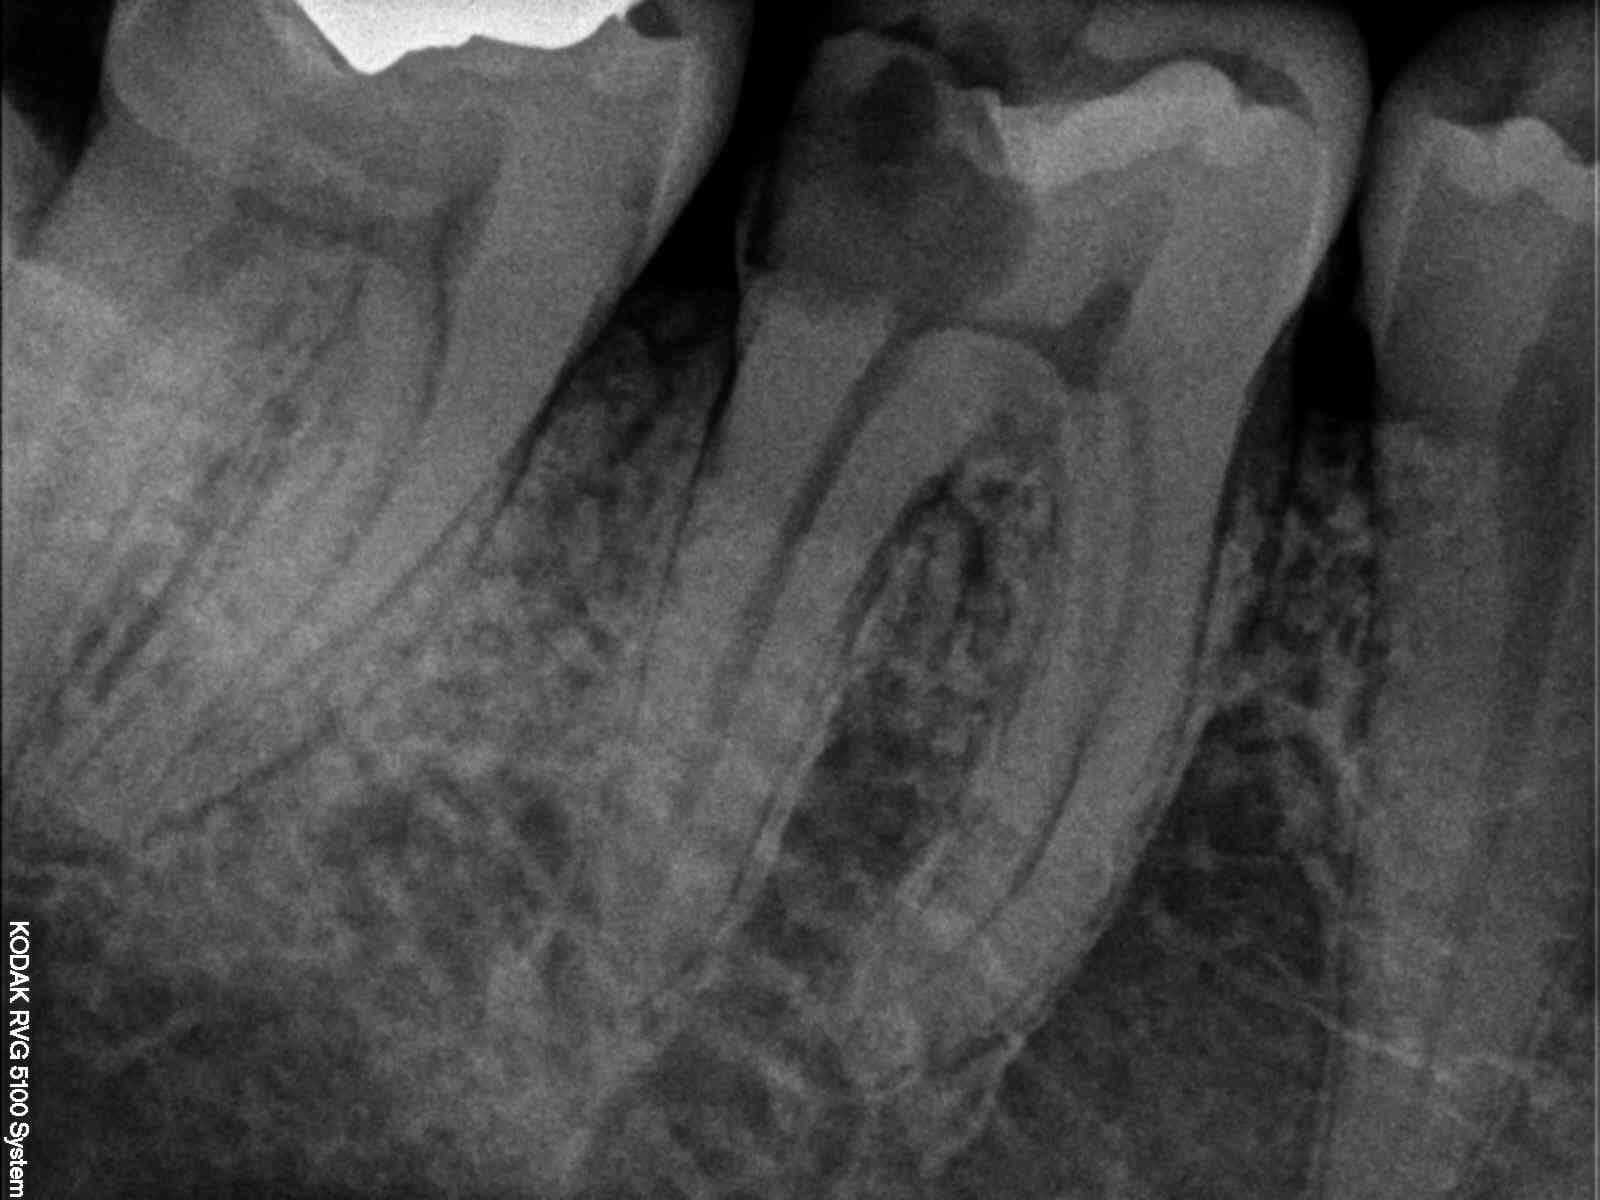

Tu vois celui là a consulté parce que sa ceram posée il y a 4 mois s'est cassée ( curieux d'ailleurs pour une full zircone d'un esthétique saisissant A4 au lieu de B2 ). Il a oublié de lui soigner la 25 par contre. C'est ballot. -)

J'en ai chié à la virer mais j'ai pas pu résister à l'appel du spr 57. Pour une fois que l'endo n'était pas à reprendre. . -)